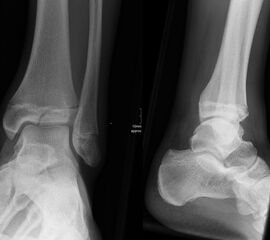

Fugengelenkfrakturen treten typischerweise vor dem 10. Lebensjahr auf, in einer Phase, in welcher die Wachstumsfugen noch weit offen sind. Dieser Frakturtyp betrifft fast ausschließlich den medialen Malleolus. Laterale Frakturen sind extrem selten, teilweise kommt es zu lateralen Bandverletzungen oder Fugenschaftfrakturen der distalen Fibula. Die Frakturlinie verläuft in einer Verlängerungslinie von der medialen Taluskante nach proximal. Häufig stellen sich Verletzungen des Innenknöchels im Röntgenbild schlechter dar, insbesondere wenn die Aufnahmen verdreht sind oder die Ebene der Fraktur bei geringer Dislokation verkippt zur Röntgenebene liegt. Besteht klinisch der geringste Hinweis auf eine Verletzung des Innenknöchels, muss aufgrund der Tragweite der Verletzung durch entsprechende Aufnahmen gegebenenfalls auch Schnittbildverfahren die Verletzung sicher diagnostiziert oder ausgeschlossen werden (Abb. 15).

„Kadiläsion“- Mediale Malleolarfraktur

Bei kindlichen Verletzungen des medialen Malleolus handelt es sich nach L. v. Laer um eine sogenannte Kadiläsion, d.h. eine Verletzung mit hohem Risiko eines schlechten Behandlungsergebnisses bei nicht korrekter Behandlung. Selbst bei optimaler Therapie ist das Risiko für spätere Wachstumsstörungen hoch, sodass diese Verletzungen nicht selten ein juristisches Nachspiel haben. Durch die Verletzung der wachstumsaktiven Zone kann es zu einem vorzeitigen Verschluss der Wachstumsfuge kommen, mit entsprechendem Fehlwachstum. Das Risiko eines vorzeitigen Verschlusses der Wachstumsfuge korreliert mit dem Ausmaß der Schädigung der wachstumsaktiven Zone. Ab dem 13. Lebensjahr wird das Risiko bei reduzierter Wachstumsaktivität zunehmend geringer.

Fugengelenkfrakturen können die Wachstumsfuge durchkreuzen (Abbildung 16a), ohne oder nur mit minimaler Beteiligung der Fuge sehr weit medial liegen (Abbildung 16b) oder durch die Fuge auslaufen (Abbildung 16c). Relevant für die Wachstumsprognose ist weniger die Form der Fraktur, sondern das Alter des Patienten zum Zeitpunkt des Traumas sowie das Ausmaß der Schädigung der Wachstumsfuge, wobei eine Korrelation mit dem Ausmaß der Dislokation besteht.

THERAPIE

Behandlungsziel ist die exakte Rekonstruktion der Gelenkfläche sowie die Minimierung des Risikos einer späteren Wachstumsstörung. Dislozierte Frakturen werden offen reponiert, die Osteosynthese erfolgt mit einer Kleinfragmentschraube. Finden sich viele kleine Fragmente kann eine K-Draht Osteosynthese durchgeführt werden. Wird der Innenknöchel operiert, kann bei gleichzeitiger hochgradiger lateraler Instabilität eine Rekonstruktion des lateralen Bandapparats durchgeführt werden. Fibula Frakturen stellen sich meist spontan ein, sodass hier keine zusätzliche Osteosynthese notwendig ist.